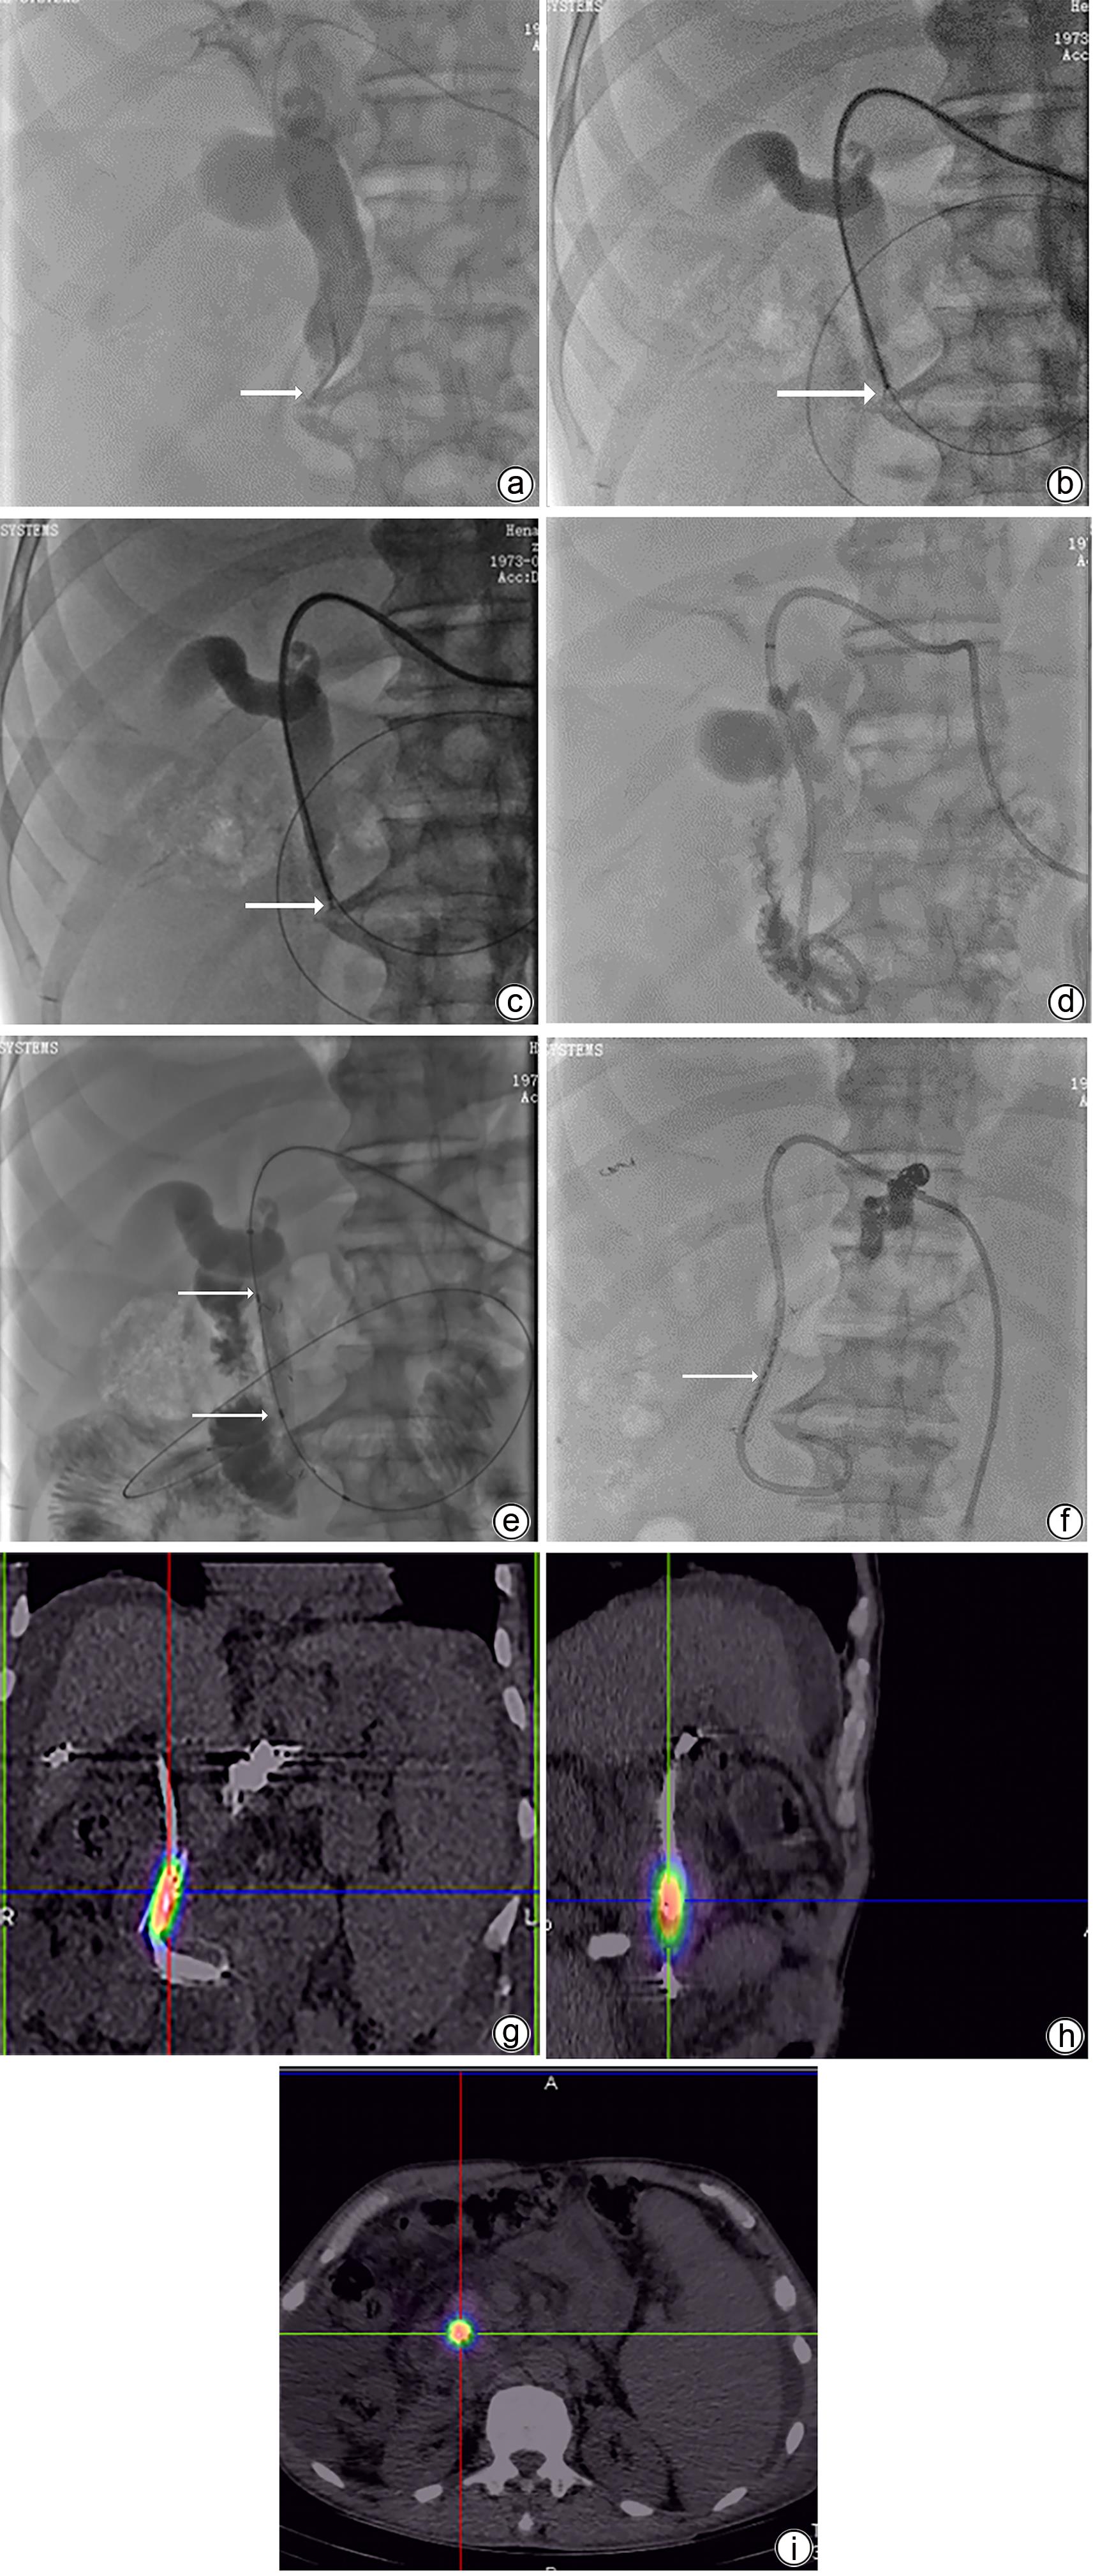

125I腔内照射联合仑伐替尼治疗进展期肝外胆管癌的效果和安全性分析

朱兴书, 陈鹏飞, 张萌帆, 李方正, 陈金威, 张文广, 段旭华, 任建庄, 韩新巍

2023, 39(10): 2406-2412. DOI: 10.3969/j.issn.1001-5256.2023.10.019

摘要(1107) HTML (319) PDF (1005KB)(56)

目的  探讨125I腔内照射联合仑伐替尼治疗进展期肝外胆管癌的有效性和安全性。  方法  回顾性纳入2018年1月—2021年11月于郑州大学第一附属医院介入科就诊的进展期肝外胆管癌患者25例。根据治疗方式分为两组,125I腔内照射联合仑伐替尼组患者13例(联合组)和单纯125I腔内照射组12例(对照组)。记录技术成功率、肝功能变化、支架通畅情况、生存期和不良事件的发生情况。正态分布的计量资料两组间比较采用成组t检验,偏态分布的计量资料两组比较采用Wilcoxon秩和检验,计数资料组间比较采用Fisher确切概率法。采用Kaplan-Meier和Log-rank检验评估生存期和支架通畅情况。  结果  两组所有患者均成功植入胆道支架和125I粒子,技术成功率100%。治疗1个月后,两组患者血清TBil、DBil、ALT和AST显著改善,与治疗前比较差异均有统计学意义(P值均<0.05)。对照组和联合组的中位支架通畅期分别为7.0和9.5个月,差异有统计学意义(P=0.022),中位生存期分别为11.5和15.6个月,差异有统计学意义(P=0.008)。治疗过程中联合组未出现不可耐受的不良事件。  结论  125I腔内照射联合仑伐替尼对比单纯125I腔内照射治疗进展期肝外胆管癌具有更好的疗效,是一种安全、有效的治疗方案。